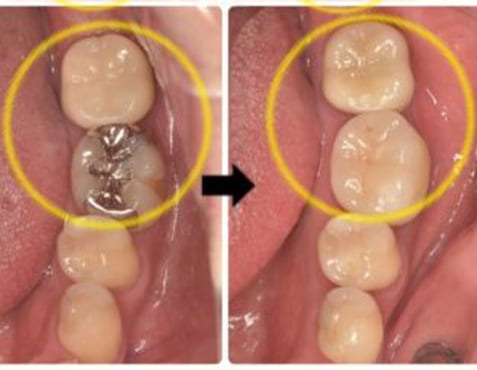

処置内容:マイクロスコープによる精密リペアとMTA根管充填

無事、骨も回復し痛みや違和感もなくなったのでオールセラミックスをいれました。当院では、他の歯科医院で抜歯と診断された歯の根管治療を日常的に行っています。高性能な治療器具の導入と、治療時にはアシストする衛生士2人を付けることによって、患者様が安心して治療を受けていただける環境を作っています。